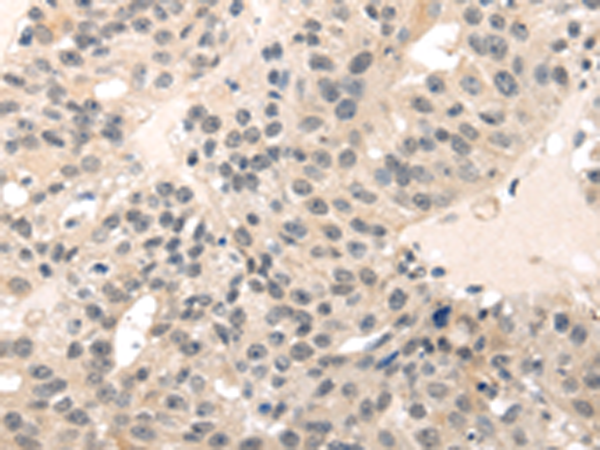

分类: 科研抗体货号: P08887别名: ECRG1应用: IHC反应种属: Human